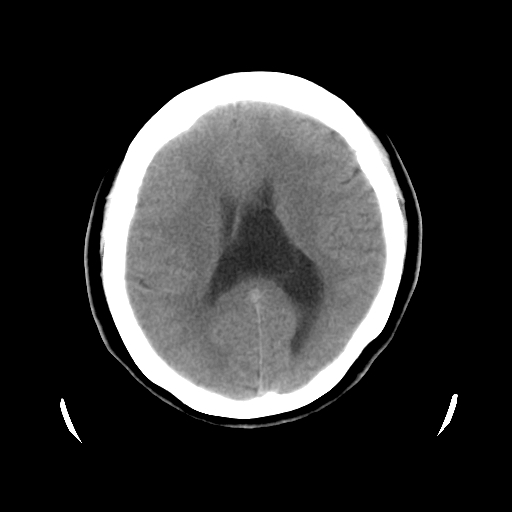

以下是引用cgf在2010-1-3 17:53:00的发言:[br]此病例多考虑:透明隔发育异常 透明隔囊肿可能性大;右侧基底节区(尾状核头)小片状低密度影考虑陈旧性腔梗[br][br]透明隔发育异常:包括透明隔间腔(第五脑室)、韦氏腔(第六脑室)、透明隔囊肿、透明隔缺如;前两者属于正常变异,后两者属于发育畸形;[br]透明隔间腔向下扩张形成韦氏腔;[br]有时透明隔间腔与透明隔囊肿很难鉴别;透明隔间腔间距一般不超过0.5cm,间距大于0.5cm时应考虑透明隔囊肿;[br]透明隔缺如为两侧脑室间隔缺如、融合成单脑室畸形,可伴有智力发育异常;[br][br]

以下是引用liaoqiang在2010-1-3 16:04:00的发言:[br]考虑侧脑室脉络丛囊肿?不除外变异的威氏腔。

以下是引用江广1996在2010-1-3 20:17:00的发言:[br]考虑变异的威氏腔。不除外侧脑室脉络丛囊肿.[br]透明隔囊肿大多数偏前,在侧脑室前角之间。